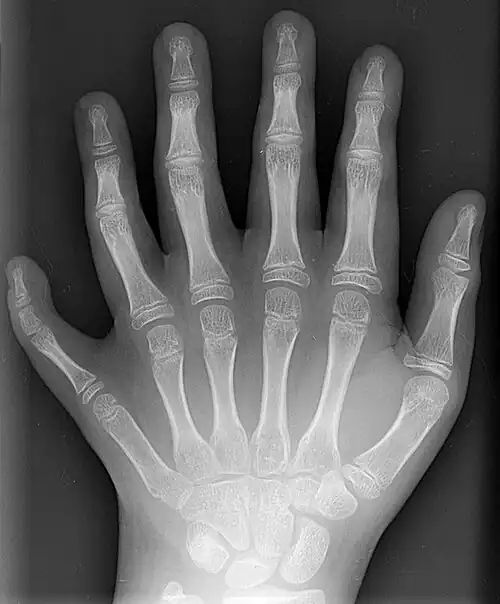

Bones of the human hand

Image showing the carpal bones

The skeleton of the human hand consists of 27 bones:[10] the eight short carpal bones of the wrist are organized into a proximal row (scaphoid, lunate, triquetral and pisiform) which articulates with the bones of the forearm, and a distal row (trapezium, trapezoid, capitate and hamate), which articulates with the bases of the five metacarpal bones of the hand. The heads of the metacarpals will each in turn articulate with the bases of the proximal phalanx of the fingers and thumb. These articulations with the fingers are the metacarpophalangeal joints known as the knuckles. At the palmar aspect of the first metacarpophalangeal joints are small, almost spherical bones called the sesamoid bones. The fourteen phalanges make up the fingers and thumb, and are numbered I-V (thumb to little finger) when the hand is viewed from an anatomical position (palm up). The four fingers each consist of three phalanx bones: proximal, middle, and distal. The thumb only consists of a proximal and distal phalanx.[11] Together with the phalanges of the fingers and thumb these metacarpal bones form five rays or poly-articulated chains.